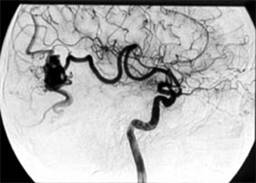

4. Суперселективная эмболизация или тромбирование АВМ. (N-бутилцианоакрилат (Hystoacryl) + жирорастворимое контрастное вещество). Рис.1.

![]() |

Рис.1 Ангиограмма больной с аневризмой левой височной доли до операции. |

Контрольная ангиограмма той же больной после эмболизации |